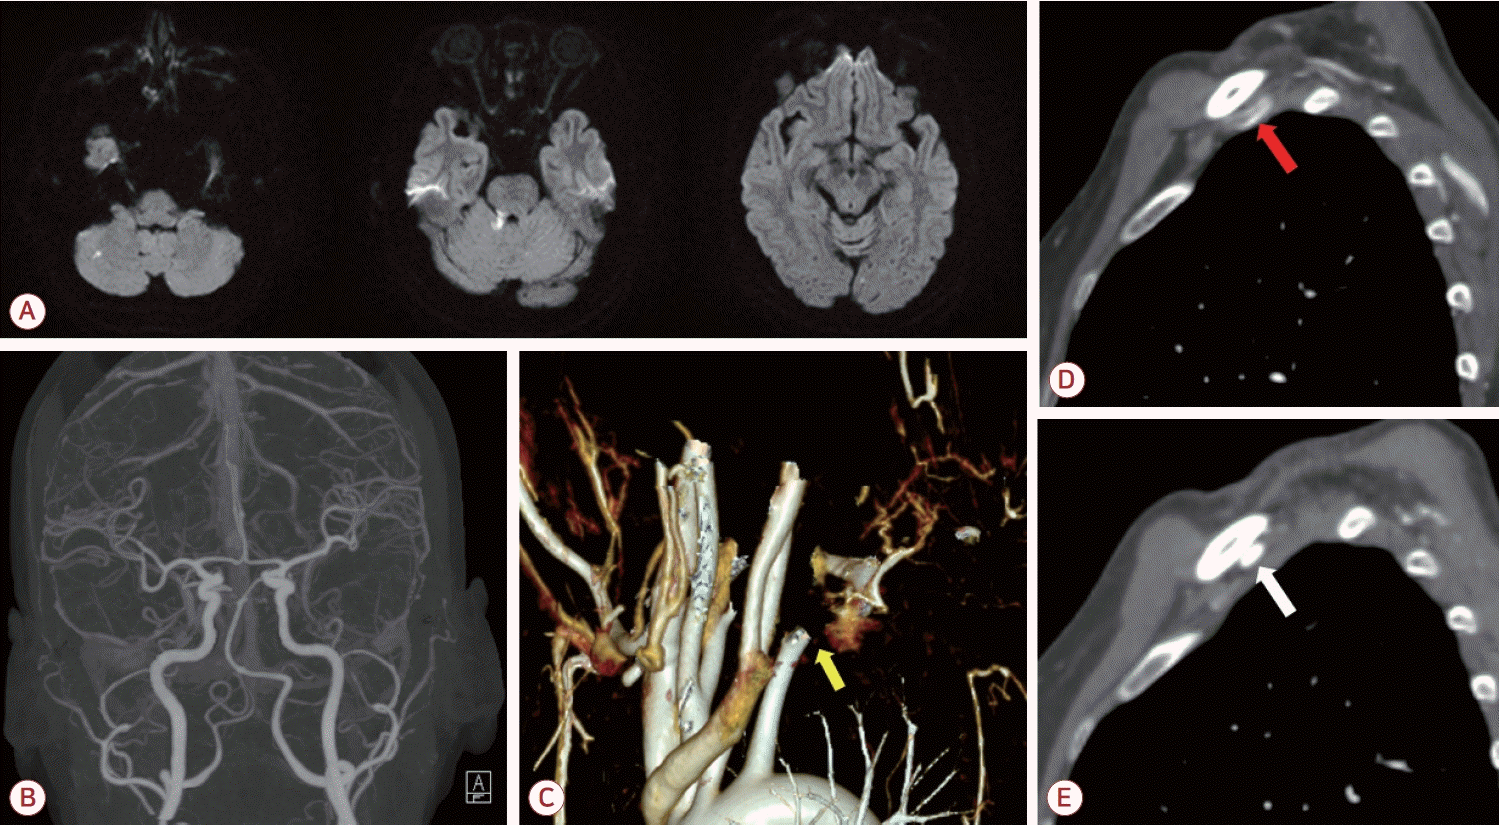

환자는 좌측 쇄골하동맥 폐색 및 동반된 뇌경색에 대해 입원하여 저분자량헤파린인 에녹사파린(enoxaparin) 1 mg/kg 하루 두 번으로 항응고 치료를 시작하였고 입원 3일차에 쇄골하동맥의 혈전색전제거술(thromboembolectomy)을 시행하였다(Fig. 2-B). 시술 후에 환자는 추가적인 뇌경색 병변이 발견되지 않았고 좌측 상지의 청색증이 호전되었으며 혈압 또한 우측과 차이를 보이지 않았다. 이후 에픽사반(apixaban) 5 mg 하루 두 번으로 약물 교체 이후 퇴원하였다. 시술 3개월 이후 추적 관찰한 혈관조영에서 이전에 보였던 혈전은 모두 제거되었고 새로운 혈전이 발생하지 않았음을 확인하였다. 또한 좌측 경추 늑골과 쇄골에 의한 쇄골하동맥의 압박 소견 및 이로 인한 말초 동맥류가 관찰되었다(Fig. 2-A, C, D). 이에 환자는 aTOS로 인한 뇌경색으로 최종 진단할 수 있었다. 환자는 항혈소판제인 아스피린 하루 100 mg으로 약물을 교체하였다. 환자에게 흉곽 출구증후군에 대해 경추늑골제거술 및 혈관성형술 등 수술적 치료를 권유하였으나 거절하여 약물 복용 유지 중에 있다.

Figure 2.

Follow up images and photos after thrombectomy. (A) Reconstruction of upper extremity computed tomography (CT) angiography showing constriction of right subclavian artery and aneurysmal change of distal part (white arrow). (B) The thrombus obstructing the right subclavian artery. (C, D) Right cervical rib (yellow arrows) and clavicle (white arrow) interrupting flow of right subclavian artery (yellow arrowhead).